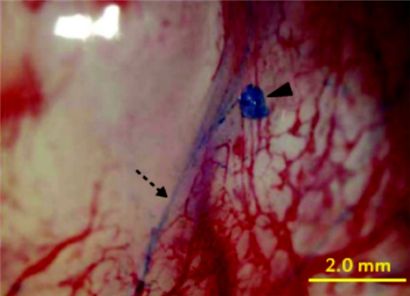

소 교수 연구팀이 암 조직 주변에서 발견했다는 프리모관. 푸른색으로 염색된 선이 프리모관이다. 국내 연구진이 프리모관의 존재를 입증해 의학의 패러다임을 바꿔놓을 수 있을지 시선이 집중되고 있다.

[아시아경제 김수진 기자]'신의'로 불렸던 명의 화타. 서기 2~3세기 중국 후한시대에 실존했던 화타는 한의학의 기초를 다진 인물이다. 그가 남긴 전설의 놀라운 면모는 서양의학보다 앞서 있는 과학성이다. 화타는 외과수술에도 뛰어났고, 그가 수술 중 통증을 줄이기 위해 만들었다고 전해지는 '마취산'은 세계 최초의 마취제다. 당시 광릉 태수였던 진등이 소화불량을 호소하자 화타는 '날것을 먹어 생긴 병'이라며 기생충약을 처방해주었다고 한다. 날것을 먹으면 기생충에 감염될 수 있다는 현대적 의학 상식을 발견할 수 있는 얘기다. 현대에 이르러 한의학의 과학성은 또 다시 시험대에 오른다. 형체가 없는 '기'로 통용됐던 한의학의 원리를 과학으로 증명하려는 시도가 이어지고 있다. 그 중 하나가 '봉한관(프리모관)'이다. 먼저 봉한관이 어떤 것인지 알아보자. '봉한관'은 1960년대까지 활발하게 활동한 북한의 생리학자 김봉한 교수가 주창한 봉한학설 중 경락의 실제로 지목된 생체 조직이다. 한의학에서 경락은 '경맥'과 '락맥'을 합친 말로 인체 내부를 연결하는 통로를 가리킨다. 한의학의 대표적 치료법 중 하나인 침술도 경락에 바탕을 두고 있다. 경락이 지나는 지점 중 '기운이 밖으로 드러나는' 특정 지점인 경혈에 침이나 뜸을 놓아 신체 내부 기관들을 치료할 수 있다는 원리다. 허리가 아파서 한의원을 찾아갔을 때 허리뿐만 아니라 몸 전체에 침을 놓는 것은 경헐을 자극해 경락의 '흐름'을 복원시켜야 한다고 보기 때문이다. 서양의학의 눈으로 볼 때 경락은 터무니없는 얘기다. 서구권에서 침술이 의학의 테두리를 벗어난 '대체의학'으로 치부되는 이유다. 침의 효과는 전세계 78개국에서 시술되고 있을 정도로 인정받고 있지만 경락과 경혈의 실체는 오리무중이다. 피부에 놓은 침이 몸 속 장기까지 영향을 미치는 원리는 과학계와 의학계의 오랜 논증감이었다. 이 때문에 서양의학의 원리로 경락의 존재를 입증하고자 하는 시도가 뒤따랐다. 김봉한 교수는 인간의 몸 속에 혈관계와 림프계에 이어 제3의 순환계가 존재하고, 세포보다 더 작은 '산알'이 조직의 재생에 관여한다고 주장, 이와 관련해 1963년 '경락계통에 관하여', 1965년 '경락체계'등의 논문을 발표했다. 경락과 경혈이 피부뿐만 아니라 몸 속에도 존재하고 있다는 주장을 편 것이다. 또한 그는 경락경혈의 실체를 찾던 중 일종의 푸른색 염색약으로 경혈점이 염색된다는 사실을 발견한 것으로 알려졌다. 이 주장은 세계적 화제를 불러 일으켰으나 김 교수의 실험이 실패로 돌아가면서 진위가 의심되기 시작했다. 게다가 김 교수가 실종되고 북한에서 봉한학설을 폐기하면서 결국 이론 자체가 사장됐다. 봉한관의 '바통'을 이어 받은 것은 우리나라다. 1994년부터 국내에서 봉한관에 대한 연구가 재개돼 봉한관 감별법과 채취방법 등이 국내 학술지에 발표됐고 해외에서도 관심이 커졌다. 이에 따라 지난해에는 봉한관이라는 이름도 '중심(primo)'이라는 뜻의 이탈리아아인 '프리모관'으로 바꿔 본격적 연구를 이어어고 있다. 2008년에는 국내 연구진이 나노형광입자로 프리모관을 염색하는 데 성공하면서 연구가 가속화됐다. 2008년 소광섭 서울대 물리천문학부 교수 연구팀이 '트라이판 블루'로 프리모관을 염색, 가늘고 투명한 프리모관을 찾아낸 것이다.

2009년에는 암조직 주변에서 경락과 프리모관 조직이 발달한다는 것을 발견, 프리모관과 암전이의 관련성에 주목하기 시작했다. 소 교수 연구팀은 "프리모관은 암 전이의 새로운 경로일 수 있다"며 "쥐를 이용한 실험에서 암 전이가 림프 뿐만 아니라 프리모관을 통해서도 일어난다는 것이 관찰되었다"고 밝혔다. 만약 프리모관이 암 전이와 직접적 관련을 맺고 있는 것이 실제로 입증된다면 세계 의학계는 '대변혁'을 맞게 된다. 의학 교과서의 기본 개념은 물론이고 치료법까지 다 바뀌어야 한다. 프리모관에 약을 주사하면 암 조직으로만 약물을 전달해 부작용을 줄일 수 있고 약효도 최대화할 수 있다는 것이 소 교수 연구팀의 주장이다. 연구팀은 산알의 존재도 긍정적으로 보고 있다. 줄기세포의 일종이거나 '가장 강력한 원천'으로 각종 줄기세포의 유래일 수 있다는 것이다. 아직까지 증명이 되려면 멀었지만, 연구팀에서는 산알이 미국의 저명 줄기세포 연구자인 마리아수 라타작 교수가 발견한 '작은 배아 같은 줄기세포(Very small embryonic-like stem cell)'과 동일하거나 변형된 형태라는 데 기대를 걸고 있다. 프리모관 연구는 계속되고 있다. 지난 13일 한의학연구원에서 열린 국제심포지엄에서는 소 교수팀은 뇌와 척수에서의 프리모 시스템 관찰법에 관한 최근 연구동향을 발표했고 국립암센터 권병세 박사가 쥐의 간에서 발견되는 프리모 시스템 연구를 선보이는 등 7개팀이 연구성과를 내놓았다. 삼성서울병원에서는 인체의 태반과 탯줄에서 프리모관을 찾아내겠다는 연구 계획을 발표하기도 했다. 만약 프리모관의 존재가 완벽히 입증된다면 단전호흡이나 요가 등의 과학적 기전도 설명될 수 있다. '기'의 실체가 밝혀져 산업의 흐름 자체가 변할 수 있는 셈이다. '기'의 소통을 원활하게 해 주는 색의 옷을 입거나, 황토집이 건강에 좋다는 '속설'도 증명될 것이다. 서구의학에 프리모관을 접목시켜 비약적 의학발전을 이끌어내는 것도 가능해진다. 그만큼 흥미롭고 상식에 도전하는 연구다. 그러나 아직까지는 연구가 초기 단계인 데다가 '말도 안 되는 소리'라고 일축하는 기존 학계의 반발도 만만치 않다. 한 연구 관계자는 "현대의학 역시 우리 몸의 기능을 전부 설명하지 못하고 있는 게 아니냐"고 반문하며 "프리모관이 무엇이며 역할은 무엇인지 조심스럽게 접근하는 중"이라고 말했다. 김수진 기자 sjkim@<ⓒ세계를 보는 창 경제를 보는 눈, 아시아경제(www.asiae.co.kr) 무단전재 배포금지>